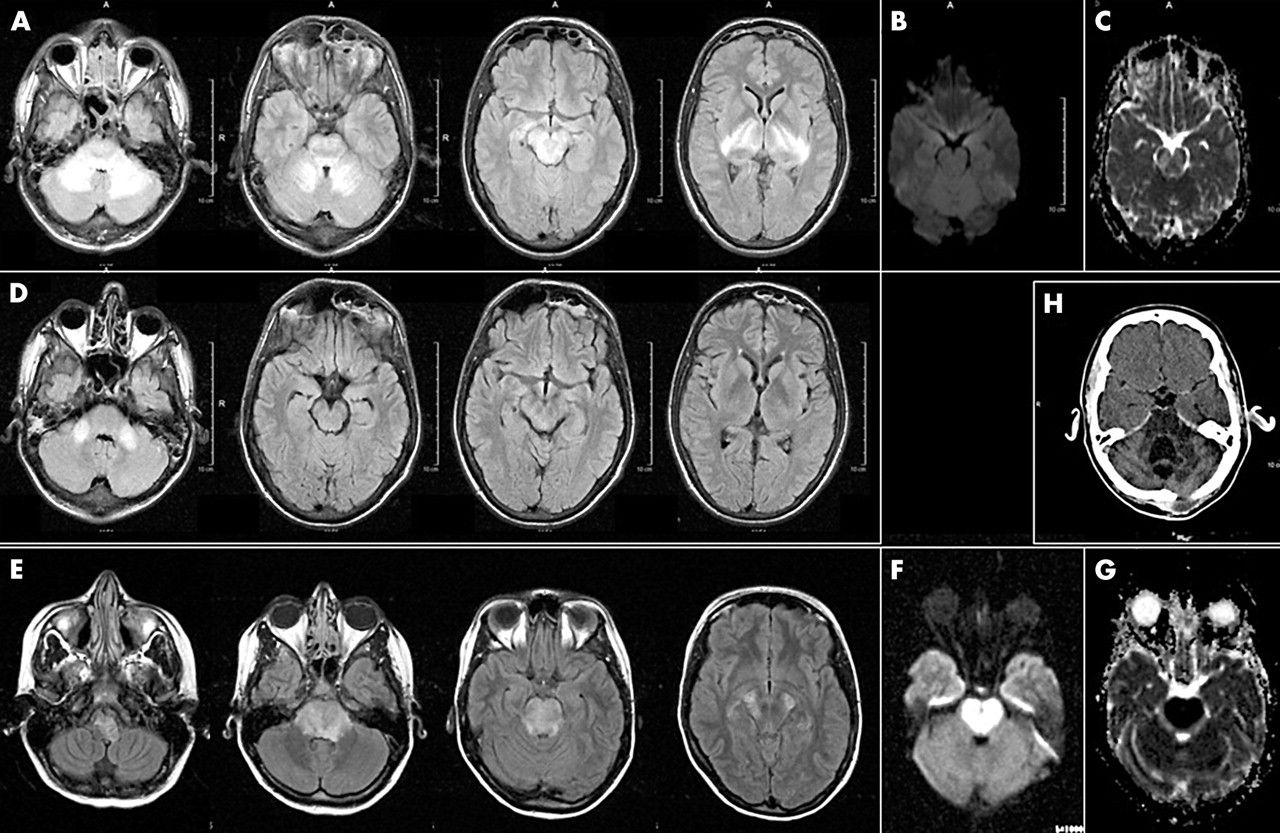

تصویربرداری دیفیوژن (DWI) نوعی تصویربرداری MR است که بر اساس اندازه گیری حرکت تصادفی براونی مولکول های آب درون یک واکسل از بافت است. به طور کلی و ساده تر ، بافت های بسیار سلولی یا آنها که تورم سلولی دارند ضرایب دیفیوژن کمتری از خود نشان می دهند.تصویربرداری دیفیوژن به ویژه در خصوصیات تومور و ایسکمی مغزی مفید است. اصطالح “تصویربرداری دیفیوژن” برای نشان دادن موارد مختلفی استفاده می شود: نقشه دیفیوژن ایزوتروپیک (آنچه بیشتر رادیولوژیست ها و پزشکان

تصویربرداری عصبی گلیوبلاستوما

تصویربرداری عصبی گلیوبلاستوما تصویربرداری عصبی نقشی اساسی در تشخیص اولیه و نظارت بعدی بر درمان های چند حالته ارائه شده به بیماران مبتلا به گلیوبلاستوما – بدخیم ترین نوع سرطان مغز دارد. محققان توصیفی جامع از تصویربرداری عصبی بالینی پیشرفته برای گلیوبلاستوما ارائه می دهند. آنها مفاهیم اساسی و آخرین کاربردهای تصویربرداری عصبی ساختاری بالینی و همچنین آخرین نوآوری ها و تکنیک های آینده برای تصویربرداری عملکردی بیماران گلیوبلاستوما را پوشش می دهند. گلیوبلاستوما (GBM) شایعترین نئوپلاسم اولیه داخل